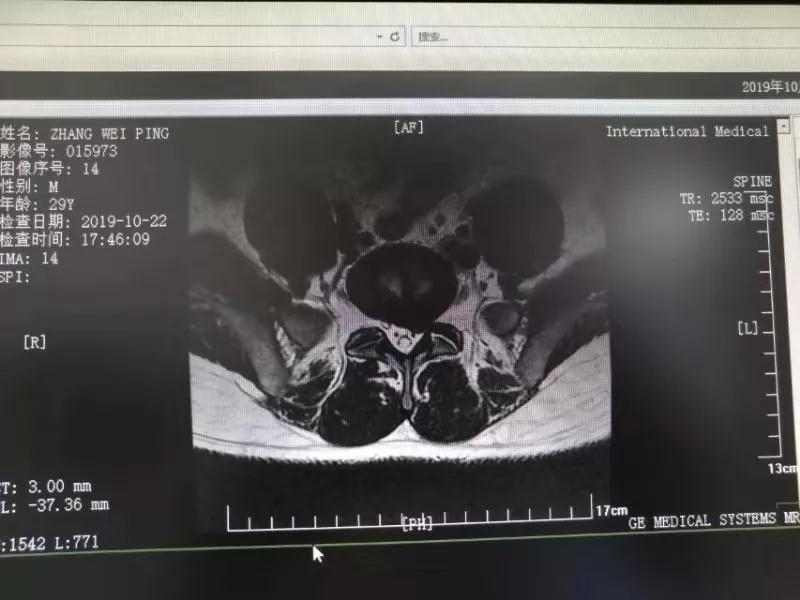

10月25日,29歲的患者小張了解到西安國際醫(yī)學(xué)中心骨科醫(yī)院專家云集,一大早便在家人的陪同下,來到西安國際醫(yī)學(xué)中心骨科醫(yī)院就診。“我腰痛持續(xù)2年多,最近感冒后腰痛癥狀明顯加重了。”小張面露苦楚,因為長期腰痛、左下肢放射性疼痛,她晚上睡覺不能平躺,經(jīng)常疼得睡不著,需要口服止痛藥物才能有所緩解。走路走不了多遠就開始腿抽的疼,嚴重影響到工作和生活。

結(jié)合患者的檢查以及年齡情況,王自立副院長推薦讓專門研究椎間孔鏡技術(shù)王雄勛主任給小張做微創(chuàng)的椎間孔鏡手術(shù)。該手術(shù)創(chuàng)傷很小,不影響脊柱的穩(wěn)定性,尤其適合于椎間盤突出的年輕患者,懷著對骨科醫(yī)院專家的信任,小張與家人商議后,接受手術(shù)治療。